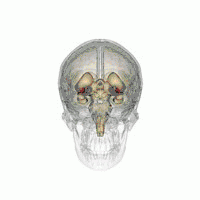

The leads are two coiled wires insulated in polyurethane with four platinum-iridium electrodes that allow delivery of electric charge from the battery pack implanted in the chest wall. The battery is usually situated subcutaneously below the clavicle and rarely in the abdomen. The leads, in turn, are connected to the battery by an insulated extension wire which travels from the chest wall superiorly along the back of the neck below the skin, behind the ear, and finally enters the skull through a surgically made burr hole to terminate in the deep nuclei of the brain.[20] Microelectrodes (usually 1–5) are delivered through the burr holes. A combination of microelectrode recordings, microstimulation, macrostimulation, and neurophysiological mapping at the level of single neurons or local neuronal populations through local field potential analyses are used to increase specificity of placement for the most precise neurophysiologic effect possible.[2]

DBS leads are placed in the brain according to the specific symptoms to be addresses and implantation may take place under local or general anesthesia. A hole about 14 mm in diameter is drilled in the skull and the probe electrode is inserted stereotactically, using either frame-based or frameless stereotaxis.[22] During the awake procedure with local anesthesia, feedback from the individual is used to determine the optimal placement of the permanent electrode. During the asleep procedure, intraoperative MRI is used to image the brain during device placement.[23] The installation of the IPG and extension leads occurs under general anesthesia.[24]